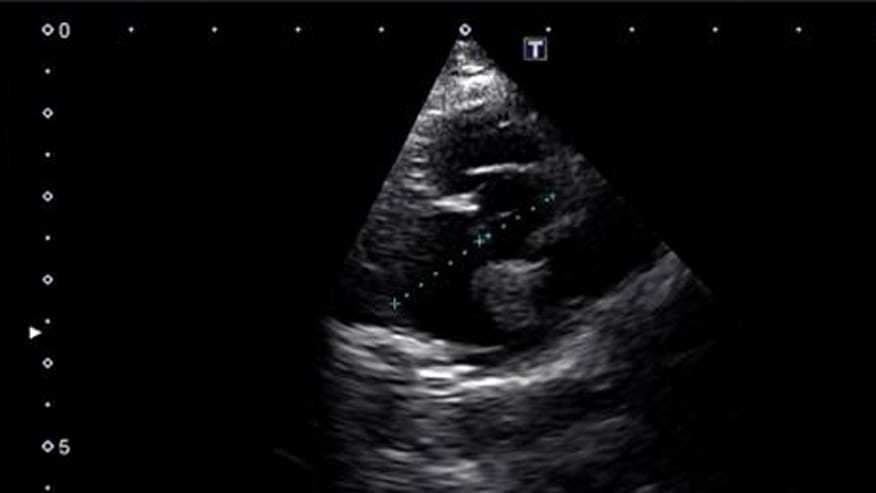

• 876x493 encina echocardiography

An echocardiogram is an ultrasound (sonogram) exam of the heart. Many times both radiographs (X-rays) and ultrasound of the heart are recommended for best evaluation of heart disease. X-rays show the size, shape and position of the heart and the ultrasound allows your veterinarian to see the internal structure and function of the heart.... Read more